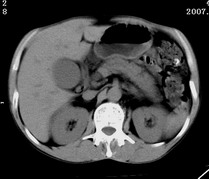

以下是引用zjzjr在2007-9-15 22:24:00的发言:[br]胰头钩突略饱满,肝内外胆管略扩张,胆囊积水.建议增强扫描.

以下是引用代课学生在2007-9-16 10:20:00的发言:[br]胆总管中段以上胆管均示扩张,考虑胆总管下段/胰头部病变,建议增强或micp检查。